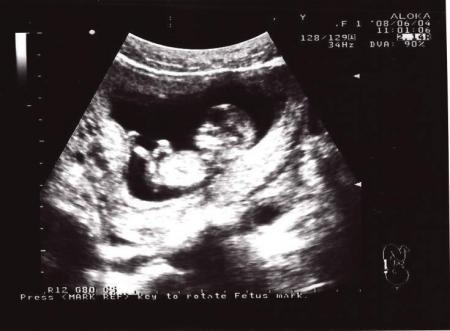

жду мальчика, 14 неделя

Первая фота

Ой, как интересно. Сегодня мне показали мою козявочку. Оказывается, что ему уже 12 недель. Так что у нас совпали акушерские недели и недели зачатия. Не пойму, как такое могло быть. Или просто месячные начались, а я уже была беременна… и поэтому я так рано почувствовала беременность. Хотя в 7 акушерских ставили где-то 5-6 эмбриону.

Ориентировочно ПДР 15 декабря. А я хотела Козерожку :)

А вот мы